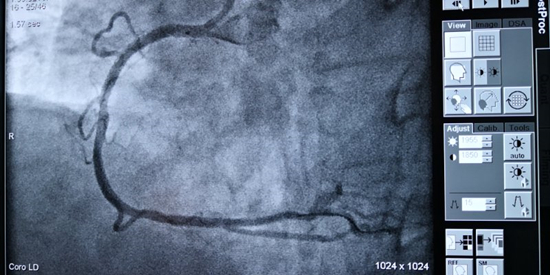

在心内科主任、胸痛中心负责人熊春林的带领下,胸痛中心介入团队紧密配合,手术顺利进行。造影证实患者发病的罪魁祸首是血管右冠近段完全闭塞,医生们立即送入导丝、球囊开通血管,并成功植入支架1枚,使患者转危为安。

支架植入术后